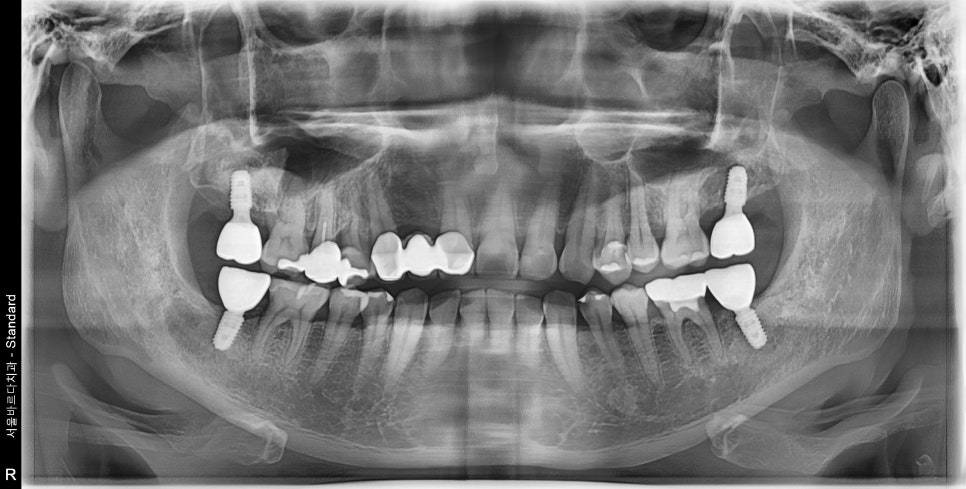

맞춤 장치를 제작하여 네비게이션 임플란트로 진행하신 후 사진입니다.

미리 술전에 임플란트 식립 위치를 확인하니

주요 신경관들과 상악동과의 위치관계 등 해부학적 구조물을 피해

뼈 자리가 좋은 곳에 완벽히 식립되었습니다.

오른쪽 위, 아래 같은 경우에는 장기적으로 없던 치아 위치 포함

양쪽으로 보철물이 다 들어가 어색하실 수 있음에도

식사하시기에 훨씬 용이하다고 하셨습니다.

본원 의료진들도 좋은 결과에 뿌듯해 했습니다.^^